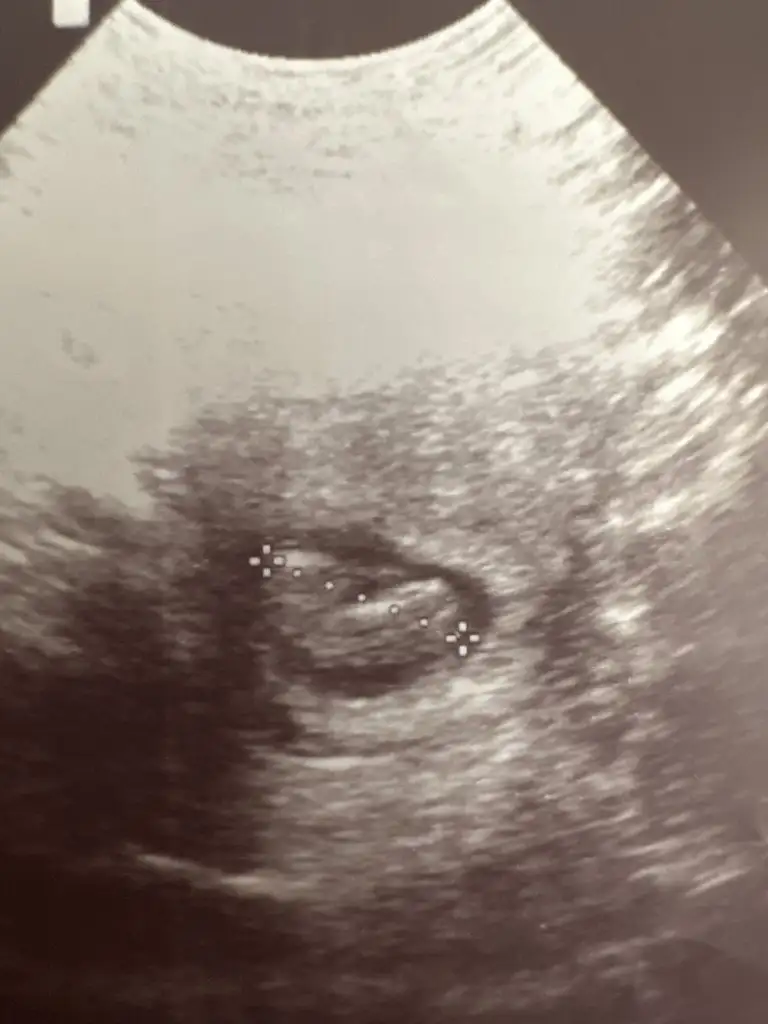

Bakalım yarın belki görür 11+2 yarınDaha belli etmez kuzum sen yine at resim gelince kararsız kaldıysam derken çok güvenme kuzum![]()

Evet kuzum öyle duruyor plesentasına göre bak şu sag taraftaki

Ayyyy çok heyecanlıyımEvet kuzum öyle duruyor plesentasına göre bak şu sag taraftaki

Keseyi saran beyazlık var ya o plesentası ona göre kız eger süpriz yaparsa bilemem![]()